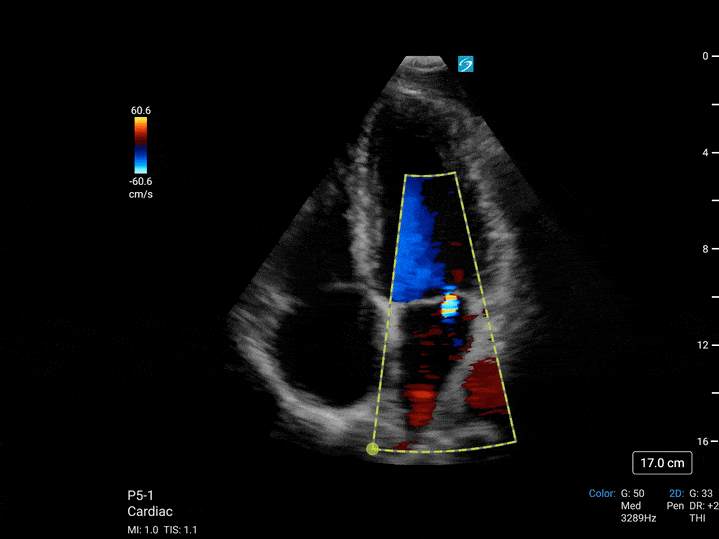

- Sektörde bir ilk olan kardiyak resüsitasyon ve akciğer muayene türleri de dahil olmak üzere T8-3 transözofageal dönüştürücü ile kardiyak ve akciğer değerlendirmelerini sorunsuz bir şekilde entegre edin